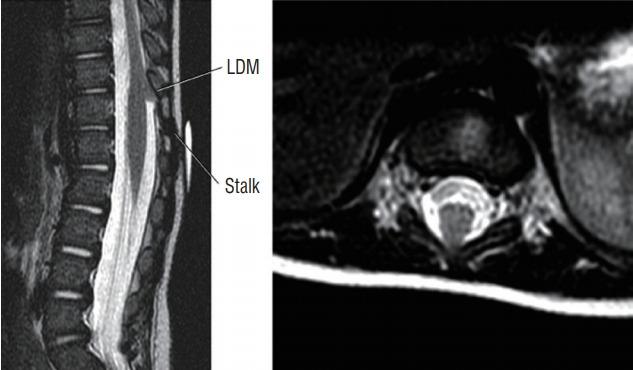

Spinal dysraphic lesions due to focal nondisjunction in primary neurulation are commonly encountered in paediatric neurosurgery, but the "fog-of-war" on these conditions was only gradually dispersed in the past 10 years by the works of the groups led by the senior author and Prof. Kyu-Chang Wang. It is now clear that limited dorsal myeloschisis and congenital spinal dermal sinus tract are conditions at the two ends of a spectrum; and mixed lesions of them with various configurations exist. This review article summarizes the current understanding of these conditions' embryogenetic mechanisms, pathological anatomy and clinical manifestations, and their management strategy and surgical techniques.

由于原发性神经管形成过程中的局灶性不分离导致的脊柱裂病变在小儿神经外科中很常见,但在过去10年中,由资深作者和王宇辰教授领导的团队的工作才逐渐驱散了这些病症上的“战争迷雾”。现在已经明确,有限性背侧脊髓裂和先天性脊柱皮样窦道是同一谱系两端的病症;并且存在各种形态的它们的混合病变。这篇综述文章总结了目前对这些病症的胚胎发生机制、病理解剖和临床表现,以及它们的治疗策略和手术技术的认识。